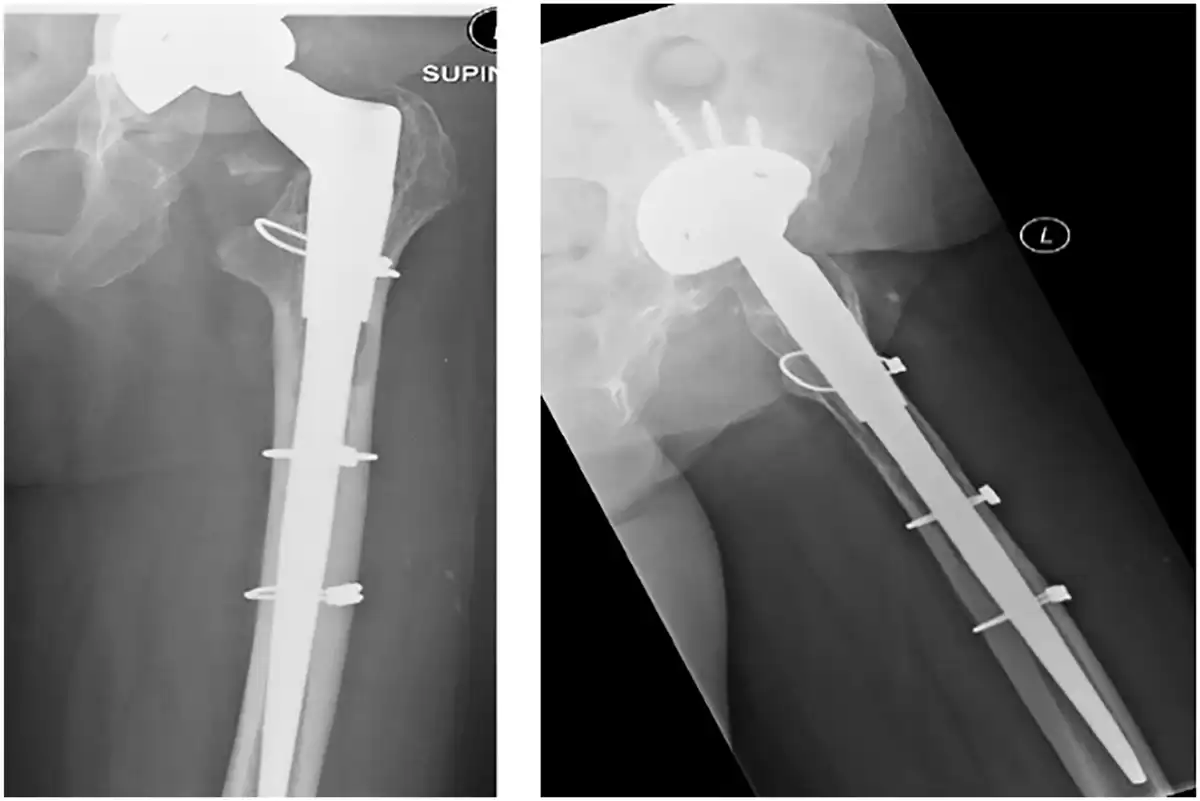

Review of radiographs revealed full integration of the cortical window in 21 cases. The earliest time to integration was 4 months. The following plain radiographs of a patient revised for aseptic loosening at day-1 and at 12 months post-surgery, respectively (Figures 7 and 8).

Figure 8

AP and lateral radiographs day-1 post-surgery. The femoral window cannot be appreciated on the AP view as it overlies the femoral component The superior and inferior transverse limbs of the cortical window are visible on the lateral view. Note proximal cerclage wire applied to prevent fracture propagating to the window whilst inserting the revision femoral stem.